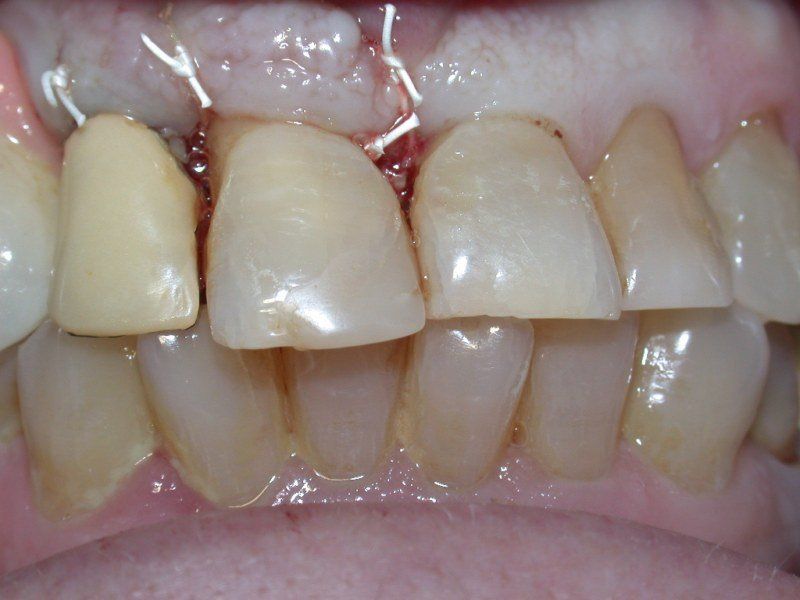

3° Caso: retrazioni gengivali